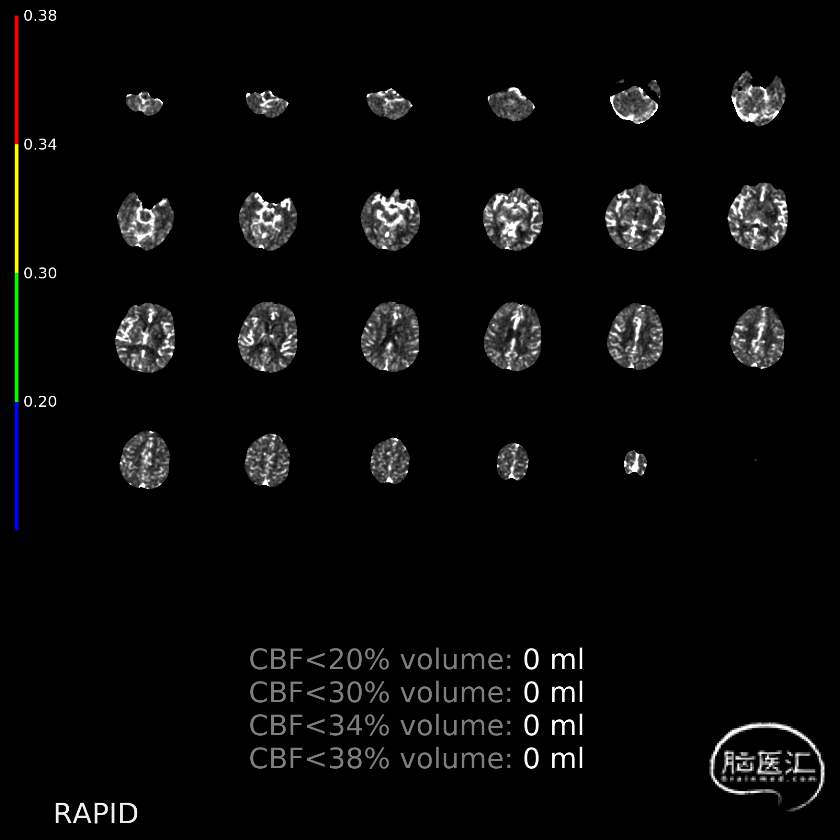

CTP